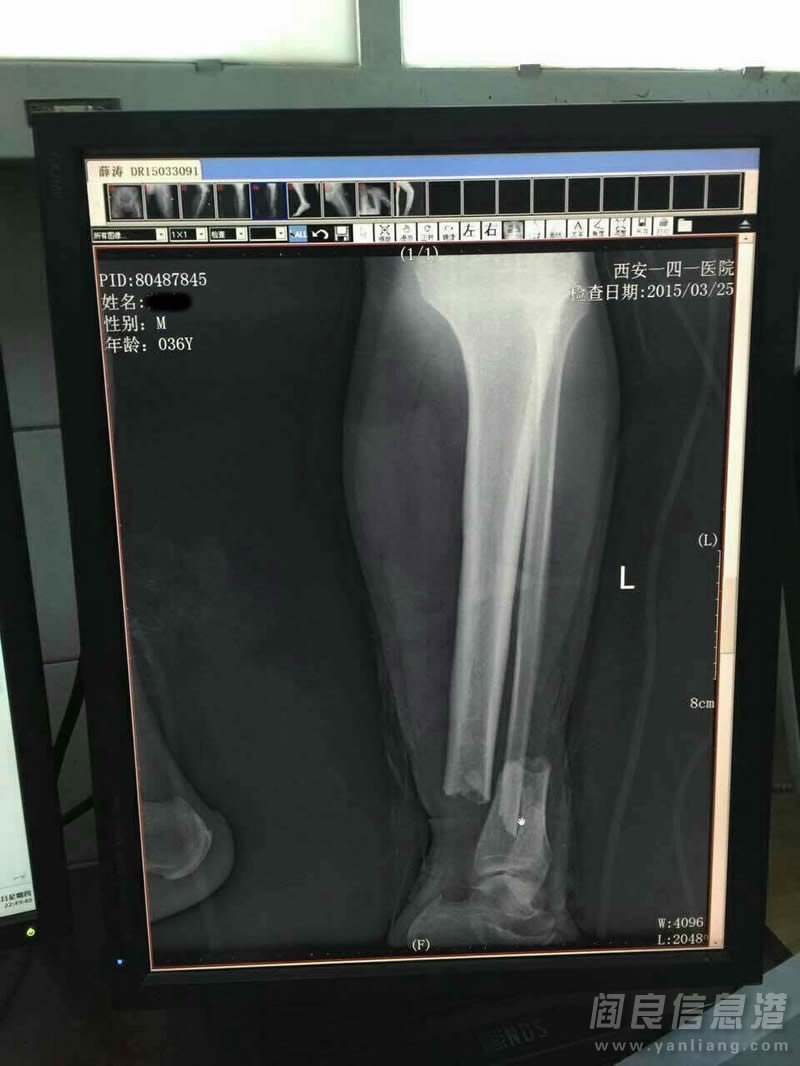

3.25宝马被撞当事人脾脏已经摘除,全身多处严重性骨折